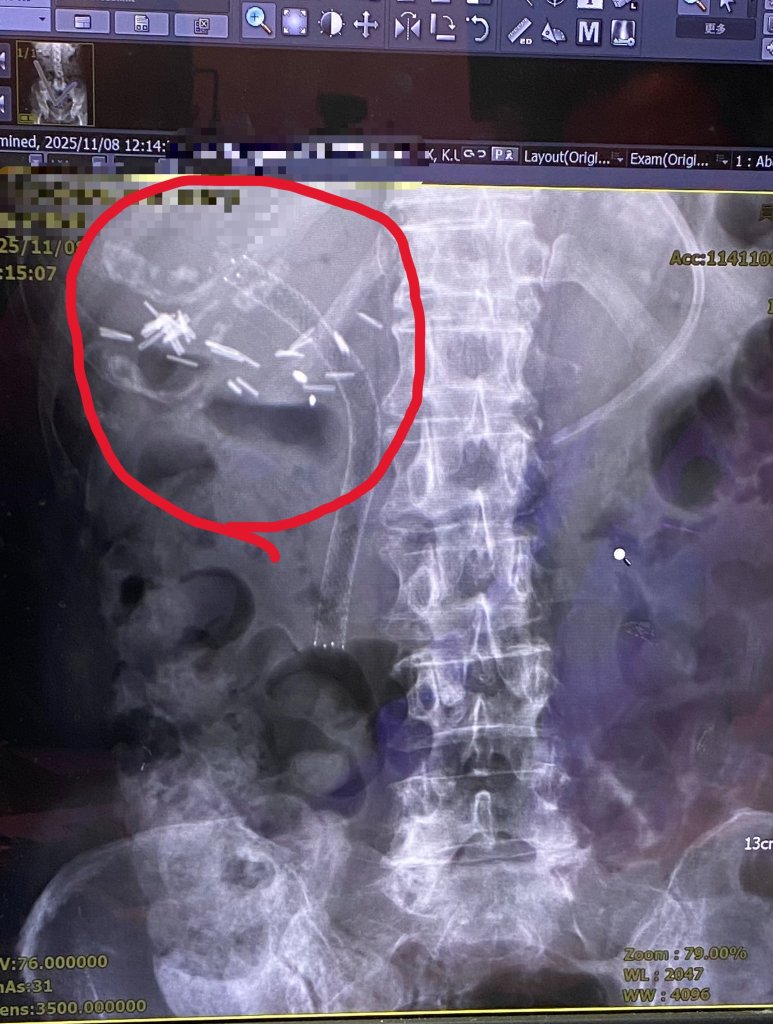

罹癌婦人膽道塑膠支架阻塞 發燒、噁心 置換金屬支架後脫離險境

70多歲婦人因腹痛、發燒,到員榮醫療體系員榮醫院就診,胃腸肝膽科醫師曾宇辰發現患者先前在其他醫院置放的膽道塑膠支架被膽汁阻塞,造成肝內膽管擴張。手術團隊移除塑膠支架後,以精準技術導管通過狹窄處,順利完成置放金屬膽道支架,讓膽汁排出,患者術後恢復良好。-